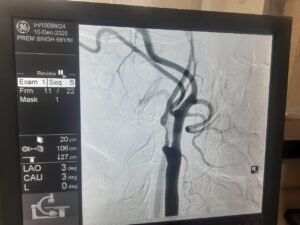

एक साल पहले प्रेम सिंह को स्ट्रोक हुआ था, जिससे उनके शरीर के बाएं हिस्से में कमजोरी आ गई थी। हालिया जांच में पता चला कि उनकी दाहिनी कैरोटिड आर्टरी में 95-99% तक गंभीर रुकावट थी, जो भविष्य में फिर से स्ट्रोक का बड़ा कारण बन सकती थी।

डॉक्टरों की मल्टीडिसिप्लिनरी टीम ने स्टेंट लगाने के बजाय सर्जरी को अधिक सुरक्षित विकल्प माना, क्योंकि रक्त नली में मौजूद प्लाक बहुत नरम और नाजुक था, जो टूटकर मस्तिष्क तक पहुंच सकता था। इसलिए Carotid Endarterectomy की सिफारिश की गई, जिसमें गर्दन की धमनी को खोलकर जमा प्लाक को सावधानी से निकाला जाता है।

सर्जरी डॉ. रोहित चौहान (सर्जन, जीबी पंत अस्पताल दिल्ली से प्रशिक्षित) द्वारा की गई। ऑपरेशन के दौरान Pruitt–Inahara Shunt जैसे विशेष उपकरण का उपयोग किया गया, जिससे सर्जरी के दौरान मस्तिष्क में रक्त प्रवाह निरंतर बना रहा और स्ट्रोक का खतरा न्यूनतम रहा। सर्जरी में बड़े, नरम और वसा युक्त प्लाक के टुकड़े निकाले गए, जिससे टीम का निर्णय पूरी तरह सही साबित हुआ।